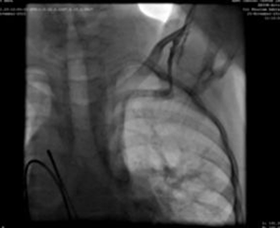

Punktion der linken Jugularvene und 5F-Angiographie-Katheter, die den Verbindungs weg zwischen Oberarmvene und Vena cava und rechtem Atrium zeigen.

Wir haben eine 9F-Lieferhülle verwendet, die vorgeschoben und in der absteigenden Aorta über dem supers teifen Führungs draht platziert wurde. Ein MemoPartTM cone shape PDA occluder 14/12 mm, was attached to the delivery cable and progressed across the delivery sheath. The placement of the occlude was proper with no residual flow.